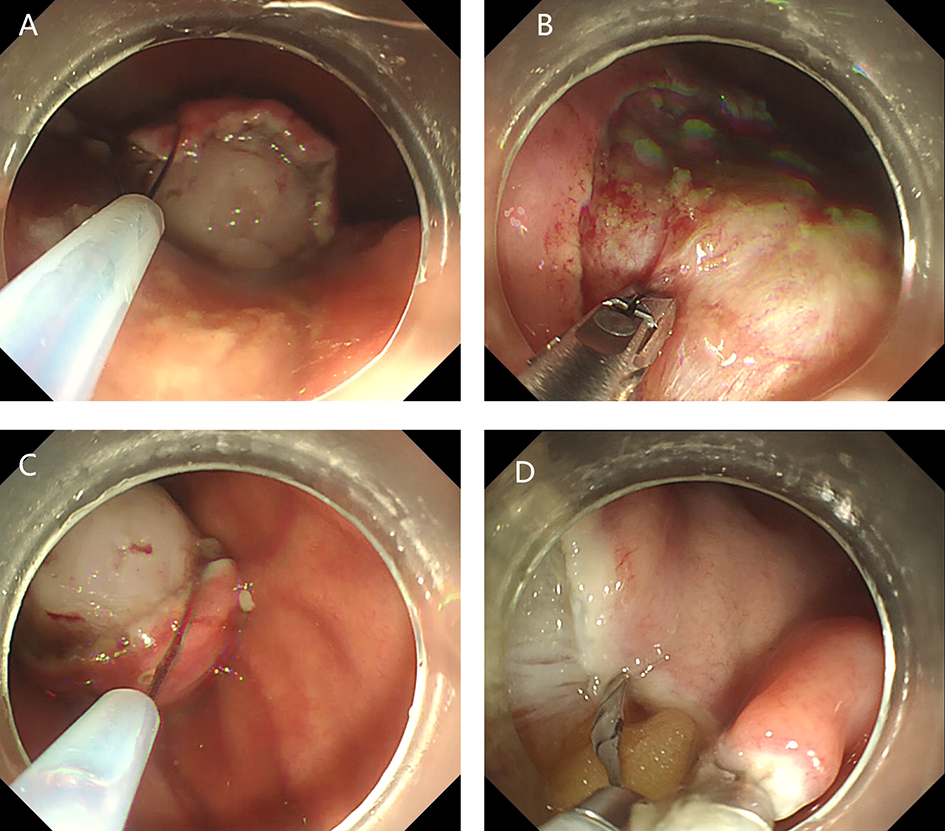

2. Submucosal tunnel endoscopic resection (STER). STER is a new endoscopic technique for the treatment of gastrointestinal muscularis propria tumors; it is an endoscopic surgical modality evolved from POEM, which mainly applies to the excision of gastrointestinal muscularis propria tumors. In sites like the esophagus, gastroesophageal junction, gastric antrum, firstly, one starts by making a small incision in the mucosal surface, then the endoscope goes deeper into it, to create a tunnel in the submucosa, to completely remove the tumor under direct vision, while preserving the integrity of the mucous surface of the digestive tract. After complete resection of the tumor, the opening of the mucosal tunnel was closed with metal clips to avoid perforation of the digestive tract and to reduce postoperative complications such as digestive tract leakage, etc. This method has the advantages of short operation time, less trauma, less pain, low cost, and quick recovery of patients. It can completely dissect the tumor in a single operation, while maintaining the integrity of the digestive tract, and has the same therapeutic effect as classical surgery, and there is no postoperative scar on the surface of the body.